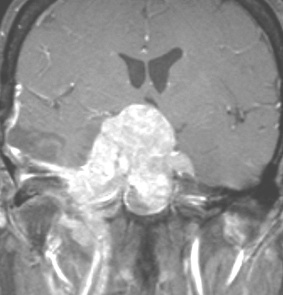

典型的な髄膜腫

この髄膜腫は中程度の大きさのものです。円蓋部髄膜種という最も多い最も手術の簡単なタイプです。麻痺や失語症やてんかんなどの症状はありません。とても美しくて若い女性の髄膜腫でしたが,子供に遺伝はしませんし,癌などと違ってタバコなどこれといった原因がなくて発生するものです。

MRIでの髄膜腫の見え方は撮影の仕方によっていろいろです。左からT1強調画像,T2強調画像,フレア画像といいます。腫瘍の横に小さく白い領域がありますが,これは脳の腫れた部分で脳浮腫といいます。髄膜腫があると周囲に脳浮腫が生じることがあります。

最も見やすいのが,ガドリニウム造影剤を注射して撮影するものです。一般的に髄膜腫は造影剤で白く映し出されます。この腫瘍は左脳側にあります。MRIの軸面という輪切りの写真では左右が逆になりますから注意してください。脳を下から見た図になっています。MRIはいろいろな方向から腫瘍を見ることができますが,右は冠状断という正面から見た図です。よく見ると腫瘍の上と下のはじっこに線状に糸を引いたように造影される部分があります。これをテールサイン(しっぽのサイン)といいます。腫瘍が硬膜に沿って延びている可能性があることを示しています。